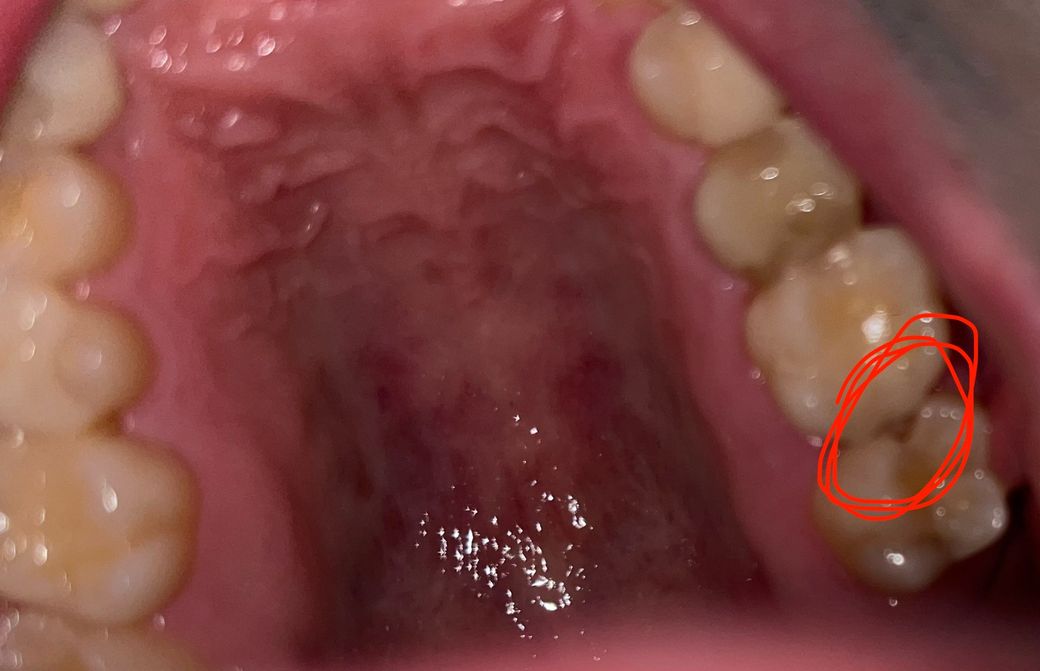

어금니에 구멍이난거같아요 음식물이 자주 낍니다

2달정도 됐는데 평소에 안아프고 밥먹을때 음식물이 자주 끼고요 혀로 느껴봤을때 살짝 뚫려있는 느낌이 들어요 충치인가요..?ㅠㅠ 심각한걸까요?

• 1번 째 사진

사진으로 보이는 이것은 인접면에 충치가 생긴 것으로 보입니다. 충치가 생기게 되고 빈 공간이 생기게 되어 해당 부위에 이물질이 계속 들어가게 됨으로써 충치가 더 진행된 것으로 보입니다. 우선 충치를 제거해야 하며 충치를 제거했을 경우 신경까지 충치가 진행되어 있다면 신경 치료가 필요할 수 있습니다.